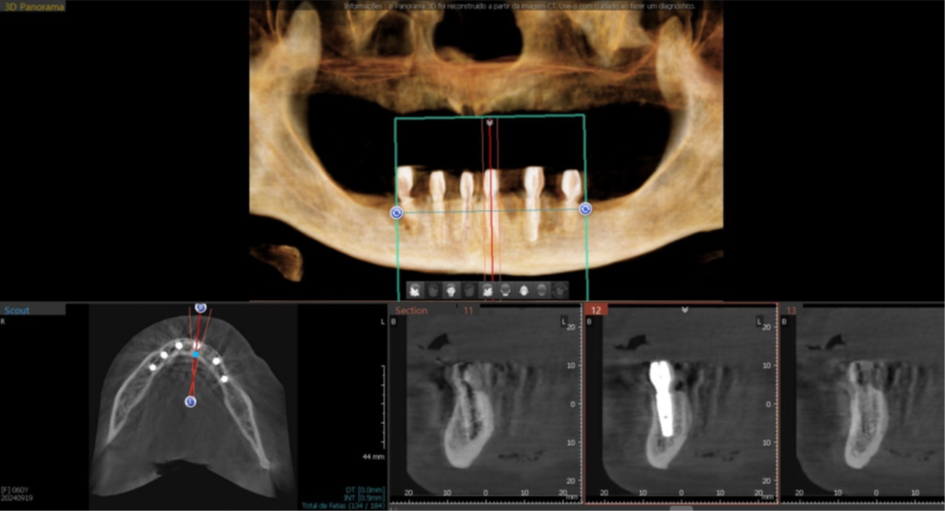

Foram planejados seis implantes nas seguintes medidas: elemento 31: 3.5x11mm; elemento 33: 3.5x11mm; elemento 35: 3.5x7mm; elemento 41: 3.5x11m; elemento 43: 3.5x11mm; elemento 45: 3.5x7mm; que foram distribuídos ao longo da mandíbula. O planejamento virtual do guia cirúrgico foi realizado em parceria com a empresa TechnoGuide, sendo posteriormente validado e aprovado para a confecção do guia definitivo.

Figura 8 – Planejamento digital do implante 31.

Figura 9 – Planejamento digital do implante 33.

Figura 10 – Planejamento digital do implante 35.

Figura 11 – Planejamento digital do implante 41.

Figura 12 – Planejamento digital do implante 43.

Figura 13 – Planejamento digital do implante 45.

Figura 18 – Corte tomográfico implante 45.

Figura 19 – Corte tomográfico implante 43.

Figura 20 – Corte tomográfico implante 41.

Figura 21 – Corte tomográfico implante 31.

Figura 22 – Corte tomográfico implante 33.

Figura 23 – Corte tomográfico implante 35.